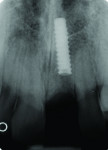

Six months after placement, the implant was restored with a custom zirconium-oxide abutment (Zirkonzahn, www.zirkonzahn.com) (Figure 4) and a ceramic crown with pink porcelain (IPS e.max® Press; Ivoclar Vivadent GmbH), which was provisionally luted with provisional cement (TempBond® NE, Kerr Dental, www.kerrdental.com) to allow the patient to evaluate the esthetics prior to definitively bonding the ceramic crown (Figure 5). After several failed attempts to remove the provisionally luted restoration at the 1-month follow up appointment, the patient did not return until 2009, at which time he presented with a missing clinical crown. The intraoral examination revealed a missing crown on the left maxillary central incisor, as well as an abutment, which was in the patient’s possession (Figure 6). The radiographic examination revealed a portion of the implant inserted 27 months prior with no appreciable pathology (Figure 7). The restoration consisted of an all-ceramic crown (IPS e.max Press) luted with provisional cement (TempBond NE) to a zirconia custom abutment (Zirkonzahn) 27 months prior.

The implant body was fractured into two separate parts. The first portion consisted of the crown, which was still attached to the custom abutment, the smooth neck section, and the first 1.4 mm of the airborne particle–abraded, acid-etched (SLA) surface of the implant (Straumann AG), with a total length of 16.4 mm (Figure 6). The other portion remained in the bone, radiographically measuring 12.6 mm in length (Figure 7). The clinical examination revealed that the fractured portion of the implant body remaining subgingivally was non-movable without bleeding, pain, swelling, or purulent discharge.

The analysis of the radiographs after the first implantation and after implant fracture (Figure 3 and Figure 7) demonstrates that bone loss of about 1.4 mm occurred in the maxillary implant area. The implant fractured at the base of the osseous defect, where one loss might have made the thin implant more fracture-susceptible.